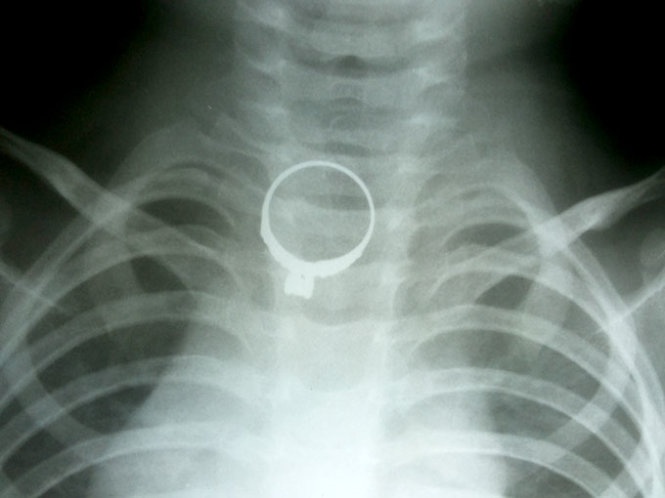

Bệnh viện hữu nghị Việt Nam – Cu Ba Đồng Hới (Quảng Bình) cho biết chiều 4/11 các bác sĩ đã gắp một chiếc nhẫn vàng trong thực quản một bệnh nhi 2 tuổi.